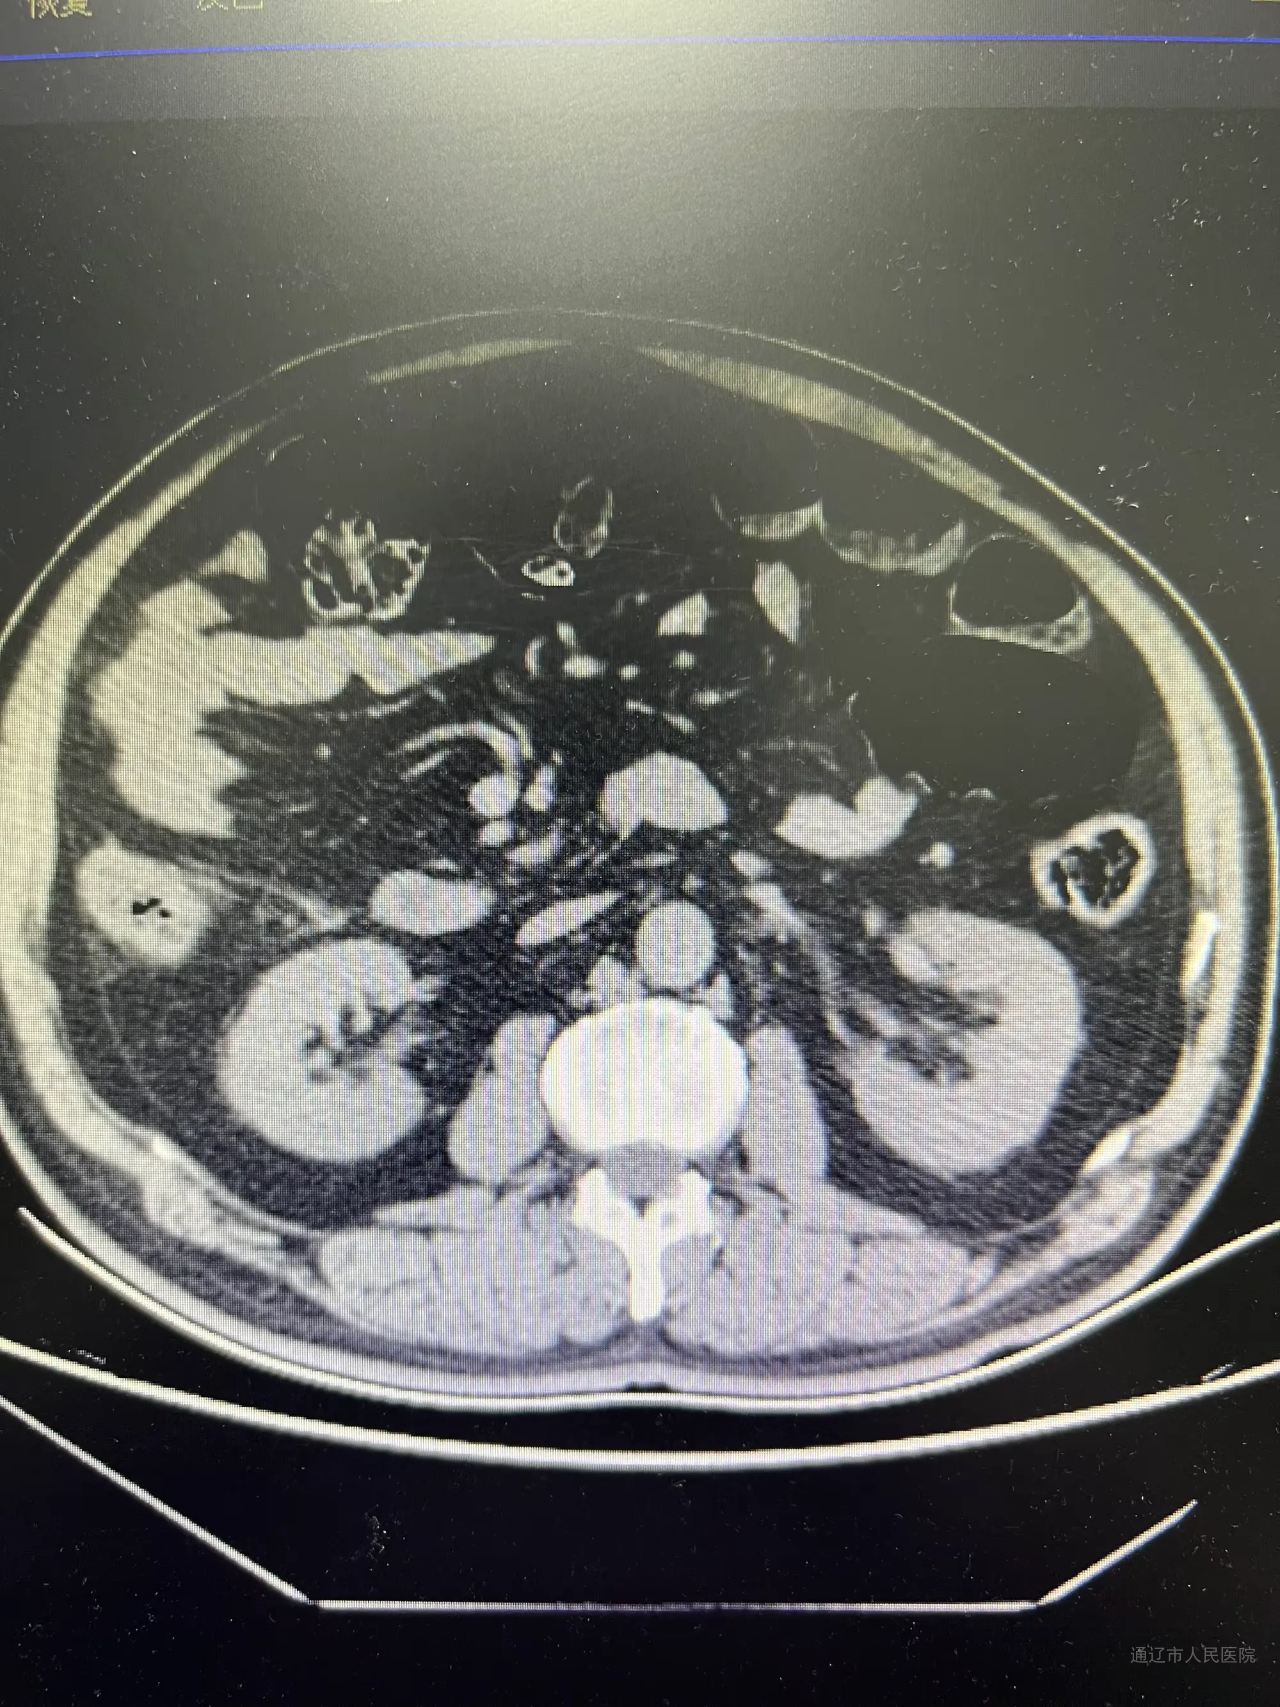

患者为63岁男性,因“间断腹痛、伴排气排便减少1天”就诊于消化内科,经治疗症状未缓解且逐渐加重。会诊后转入胃肠疝外科,腹部CT检查显示升结肠肠壁增厚,考虑恶性病变。鉴于患者腹胀明显,科室迅速完善术前准备,当日在急诊全麻下行回盲部造口术,术后患者状态明显好转。1周后,在全麻下行腹腔镜右半结肠癌根治术,手术由副院长张国友主刀,主任医师郭云峰、副主任医师刘宗旭协助完成,手术经过顺利。

梗阻前CT